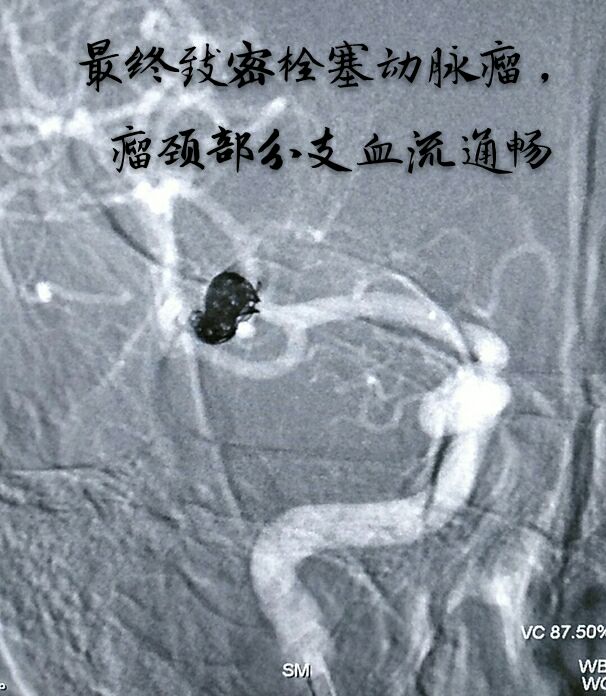

病例一:左侧颈内动脉虹吸弯大动脉瘤,宽颈,形态不规则

支架辅助+双微导管技术致密栓塞动脉瘤